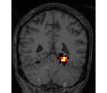

Experiments outline a tradeoff between prediction accuracy and computation time. Fig. 1 displays the relative prediction accuracy and run time. TV- predicts best on average over the various classification tasks. However, it is followed closely by social sparsity which outperforms graph-net222All differences are significant in a Wilcoxon rank test.. The SVM performs much worse than the spatial sparsity, aside from the VBM data where we find that all models perform similarly.

In terms of run time, we find that graph-net is on average 4 times faster than TV-, but social sparsity is 3 times faster than graph-net. The SVM-based decoder is 20 times faster than social sparsity, ie 240 times faster than TV-.

Finally, an important aspect of the brain decoders is whether they segment well the brain regions that support the decoding. Such a question is hard to validate, yet there is evidence that TV- is a good approach [5]. Fig. 2 displays the decoder maps for the object-recognition tasks. For these tasks, we expect prediction to be driven by the functional areas of the visual cortex [27]. Indeed, the maps outline regions in known visual areas. The graph-net maps are much more scattered and less structured than the others. Conversely, the social sparsity maps are sparser and outline a smaller number of clusters.